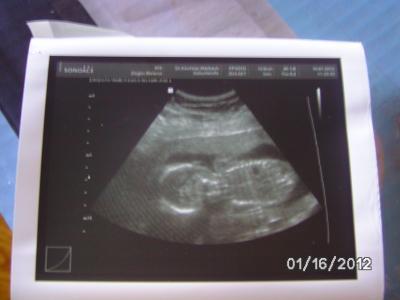

Hallo meine Lieben habe heute FA Termin gehabt,beim US war alles in Ordnung Baby wächst zeitgerecht und ist jetzt 18cm groß und 200g schwer,und heute hat der Krümmel so schön die beine auseinander gemacht und mein FA hat gleich eindeutig das Geschlecht erkannt es wird ein: MÄDCHEN JUHU *freu* Ich könnte die ganze Welt abknutschen. Ich habe mich so gefreut und mein Mann und ich haben direkt angefangen zu weinen..... Endlich nach 2 Jungs ein Mädel ich freue mich so das wir eine Prinzessin bekommen. Hier noch ein Bildchen für euch.... Ganz Liebe Grüße

Bild zu Heute FA Termin gehabt mit Outing ich ich könnte die ganze Welt knutschen:-) - Forum für Juni - Mamis